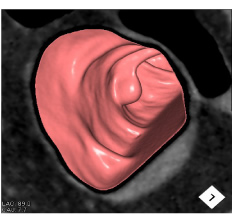

※大腸CT(仮想大腸内視鏡)

大腸CTは、内視鏡を使わない大腸検査です。大腸内視鏡と同様の前処置を行った後に、大腸を炭酸ガスによって拡張させ、新型のマルチスライスCT装置を用いて撮影することで大腸の3次元画像を簡単に得る検査です。

大腸CTは、仮想大腸内視鏡検査とも呼ばれ、内視鏡検査と比較して苦痛や違和感が少なく、短時間で検査可能で受診者の受容性が高いことから、これまで大腸の精密検査に抵抗感のあった方にもおすすめできる検査です。

• 大腸CT画像

• 3次元画像(仮想大腸内視鏡画像)